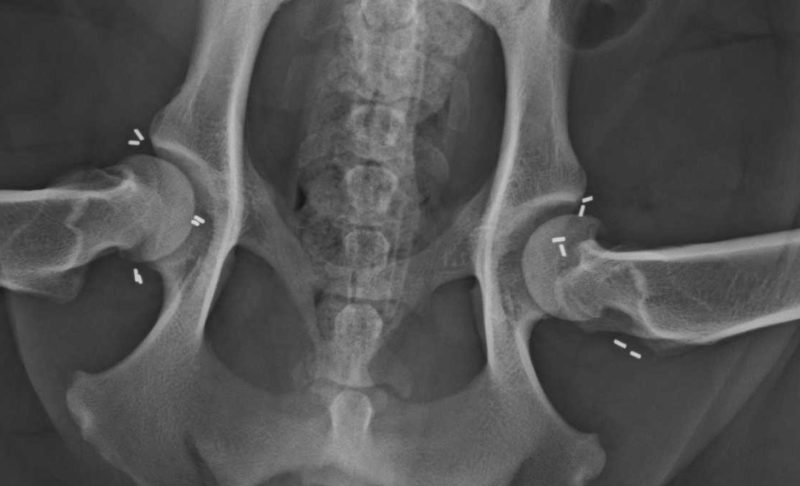

Die Goldakupunktur ist eine Dauerakupunktur mit Golddrahtstückchen, die durch die permanente Einwirkung auf die Akupunkturpunkte und -meridiane den Stoffwechsel erkrankter Gelenke und der Muskulatur verbessert und dadurch zu einer Schmerzlinderung oder -befreiung führt. Hierbei werden stiftförmige Stücke eines hochkarätigen Golddrahtes, in manchen Fällen auch Platinimplantate, an die Akupunktur- und Schmerzpunkte implantiert. Die Methode ist minimalinvasiv und bereitet dem Patienten daher keine Operationsschmerzen. Die Implantate wachsen ohne weitere Probleme im Gewebe ein und verbleiben ein Leben lang an der gewünschten Stelle. Diese schonende dauerhafte Schmerztherapie kann bei Gelenkserkrankungen z.B. Hüftgelenksdysplasie, Ellenbogendysplasie, Kniegelenksarthrosen, Wirbelsäulenveränderungen und deren Folgen eingesetzt werden. Die Methode wurde in den USA von DVM Terry E. Durkes Ende der 70er Jahre entwickelt.

Wir arbeiten mit dieser modifizierten Methode, die als ganzheitliche Orthopädie zu verstehen ist, seit nunmehr 16 Jahren erfolgreich in unserer Praxis. Die vorhergehende umfassende Diagnostik mit einer ausführlichen Gangbildanalyse und der Triggerpunktdiagnostik (Schmerzpunktuntersuchung) erfasst alle relevanten Schmerzen, auch die, die sich nur aus der Entlastung der veränderten Gelenke und damit einer Überbelastung in die anderen Gelenke ergeben. Weiterführend werden digitale Röntgenbilder angefertigt.

Vor einem Monat wurde uns „Yelle“, eine 4-jährige Cocker-Spaniel-Hündin, vorgestellt. Durch die Gangbildanalyse, der Untersuchung der Triggerpunkte und das folgende Röntgen wurde schnell klar, dass Yelle durch eine sehr lose schmerzhafte Hüfte ein deutlich verändertes Gangbild zeigte. Die Besitzer entschieden sich daher frühzeitig für eine Goldakupunktur, um Folgeschäden an den anderen Gelenken zu minimieren. Die Kontrolluntersuchung nach der Goldimplantation verlief sehr positiv - Yelle will spielen und toben. An diesem Punkt ist es wichtig, dem Muskelaufbau Zeit zu geben und den Hund noch nicht zu viel toben zu lassen. Eine geregelte Bewegung und eventuelle physiotherapeutische Unterstützung hilft, das Gangbild zu stabilisieren.